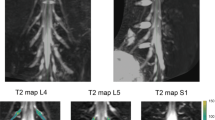

Five patients underwent MRN with T2 mapping of the distal sciatic nerve bilaterally using the 3D T2-prepared TSE sequence. These patients initially presented in the outpatient clinic with unilateral sciatica due to degenerative disc disease with disc herniation and unilateral nerve contact of degenerated disc material according to previous anatomical MRI (Fig. 5). Neuroforaminal to extra-neuroforaminal disc herniations with nerve contact affecting L4 or L5 were present in these patients (Fig. 5). A mean ODI score of 35.2 ± 10.7 was registered, with a mean pain rating according to the VAS of 7.4 ± 1.1 points. None of the patients suffered from a manifest hemiparesis according to the BMRC scale. Two patients reported previous surgery for decompression at a different level than the currently affected level 37 and 17 years ago, respectively.

Case series of patients. Sagittal and axial slices of structural magnetic resonance imaging (MRI) from a case series of five patients with unilateral sciatica due to degenerative disc disease with disc herniation and unilateral nerve contact of degenerated disc material (red circles). Furthermore, representative axial T2 maps derived from the three-dimensional (3D) T2-prepared turbo spin echo (TSE) sequence are shown for the right and left lower thigh regions, depicting the distal sciatic nerve (white squares). Mean ± standard deviation of measured T2 values of the lower sciatic nerve was 61.5 ± 6.2 ms for the affected side and 43.3 ± 2.4 ms for the contralateral, unaffected side

When discriminating between T2 values of the affected and non-affected side derived from the 3D T2-prepared TSE sequence for the distal sciatic nerve, patients showed T2 values of 61.5 ± 6.2 ms for the affected side and 43.3 ± 2.4 ms for the contralateral, unaffected side (R1). When comparing the T2 values of the affected side against the T2 values obtained in the healthy subjects, significant differences were observed for both the comparison against left-sided and right-sided normal T2 values (R1 p < 0.0001 each).